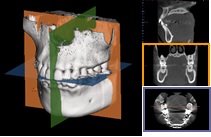

インプラント治療は顎の骨の中にインプラントを埋める治療で、顎の骨がどういう形態になっているか?神経はどの位置にあるか?隣り合う歯との関係性はどうか?などを把握するために立体的に診ることが欠かせません。

そういった立体的な把握に加え、骨質(硬さ)もわかる当院の歯科用CTは他のどの歯科用CTよりもインプラント治療に最適であるといえます。

インプラント手術支援システム「Landmark System」との連携

撮影したCTデータをインプラントシミュレーションソフト「LANDmarker」に取り込み、患者さま毎の顎の骨の硬さや形、神経の位置などをより詳細に確認しながら、診断することが可能です。